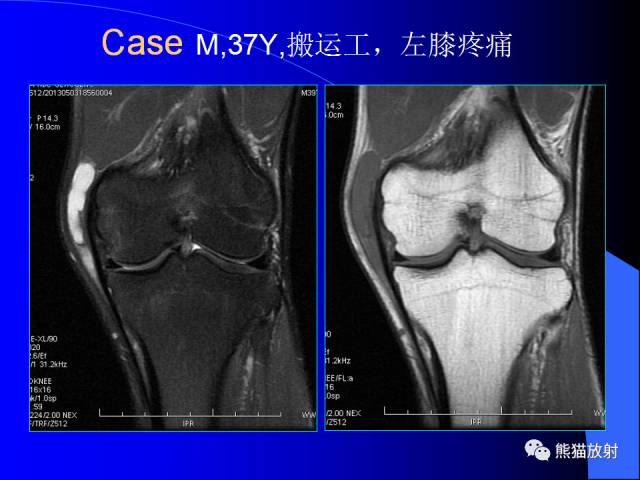

膝关节周围囊肿是较常见的病变,可以是原发的,多见于青年及儿童,囊内容物通常是黏液;也可以是继发的,多与关节腔相通,内含一般黏性的滑液,常继发于膝关节骨关节炎、类风湿关节炎、非特异性滑膜炎、半月板损伤、髌骨软骨软化症等。

腘窝囊肿是膝关节周围最常见的囊肿。